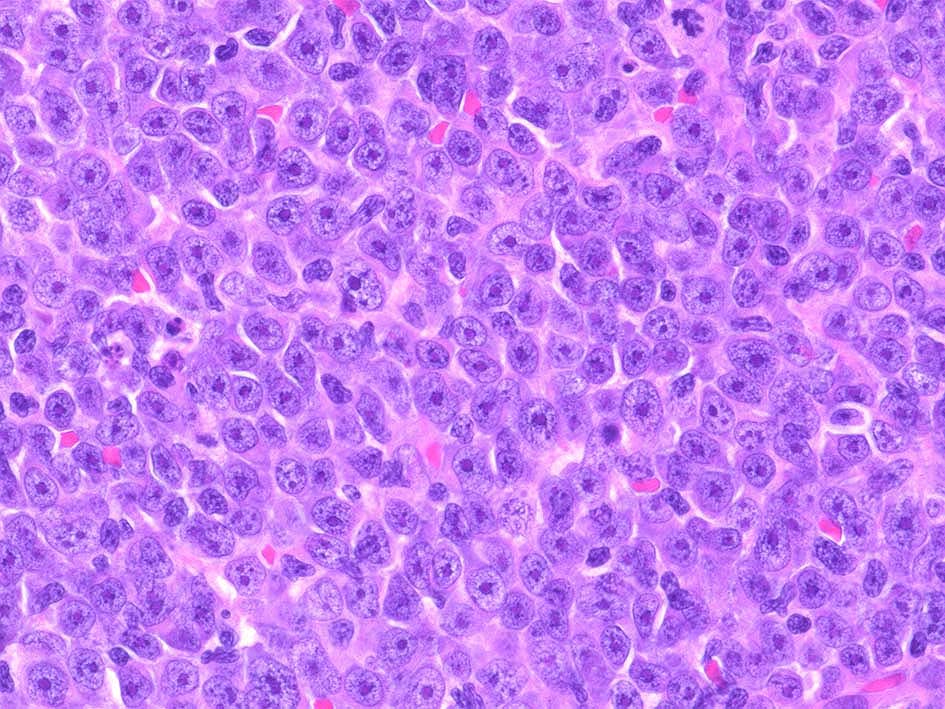

DLBCL, Not Otherwise Specified

Immunoblastic (免疫芽球型)

Centroblastic および immunoblastic variantが通常多く認められる他に, multilobulatedや anaplastic variantが認められている,しかし, これら細胞形態による臨床的意義については評価が定まっていない.*28

• 最も多くみられるtype.腫瘍細胞は胚中心, centroblastに似る. (核膜に付着するように核小体が2~4個認められる)

• 核はほぼ均一な大きさのことが多いが, ときに大小不同がめだつこともある.まれに分葉ないし多核に見える細胞が混在.

免疫芽球が混在することもある.

血液病理学者が腫瘍細胞形態に基づいてDLBCLをサブタイプ化しようと試みたが,観察者および観察者群間の再現性が乏しく, 結果として, WHOリンパ性腫瘍組織分類においてDLBCLとして単一の診断カテゴリーにまとめられている.*29